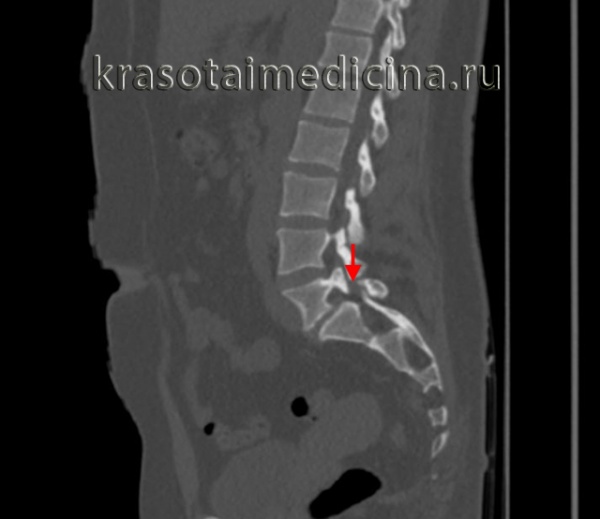

о Различной выраженности спондилолистез и фораминальный стеноз на сагиттальных реконструкциях:

- Снижение высоты межпозвонкового диска

- Дегенеративные изменения замыкательных пластинок

(Справа) КТ, сагиттальный-срезе (костный режим): задний край тела L5 находится практически на одном уровне с передним краем S1. Хорошо виден дефект межсуставной части дуги, а также признаки выраженного стеноза межпозвонкового отверстия.

КТ пояснично-крестцового отдела позвоночника. Нарушение целостности задних отделов позвонка без существенного спондилолистеза.